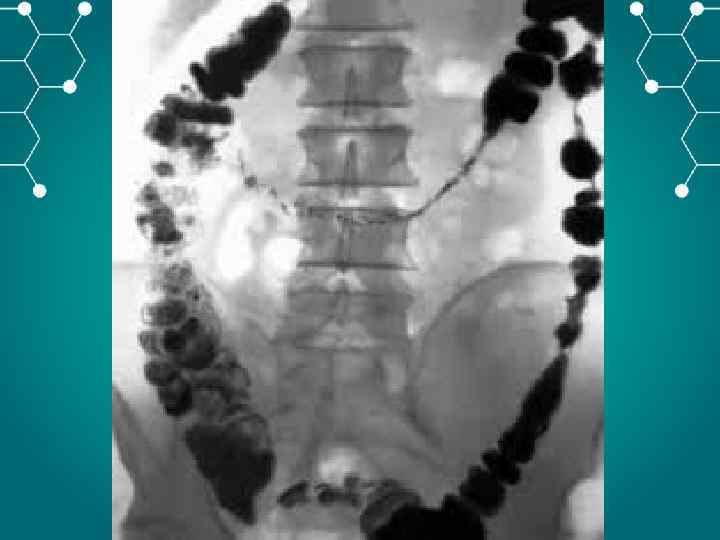

Инструментальная и лабораторная диагностика ОАК – эритроцитоз до 5 6 млн. , лейкоцитоз до 20 тыс. со сдвигом лейкоцитарной формулы влево, эозинопения. , повышение значения СОЭ. БХАК снижение уровня хлоридов с 500— 550 мг% до 400— 300 мг%, повышение остаточного азота, возможно повышение ALT AST CРБ. ОАМ – снижение количественного показателя, повышение концентрации белка. Обзорная рентгенография – наличие «кишечных арок» , «чаши Клойбера» , симптом перистости(растяжение тощей кишки). Ирригоскопия – симптом «трезубца» , видимые нарушения проходимости. Колоноскопия – визуальное определение патологии. УЗИ КТ